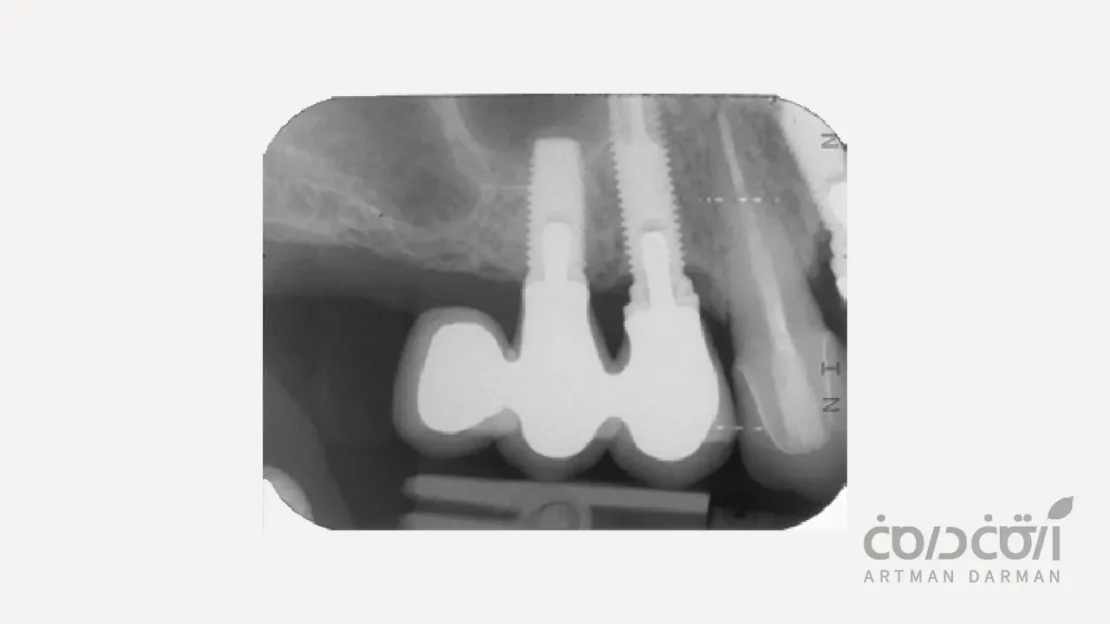

راهکار دوم استفاده از بریج بر پایه دو ایمپلنت است

این روش درمانی معمولاً برای جایگزینی سه یا چهار دندان مجاور استفاده می شود. به عنوان مثال، برای جایگزینی سه دندان، دو ایمپلنت در ابتدا و انتهای ناحیه بی دندان کاشته می شوند. سپس یک پل سه واحدی روی آن ها قرار می گیرد. اما آیا می توان از این اصل در جایگزینی دو دندان با ایمپلنت استفاده کرد؟

بله، اما نه به شکلی که تصور می شود. در شرایط بسیار خاصی که فاصله بین دو دندان از دست رفته بسیار کم باشد یا آناتومی استخوان به گونه ای باشد که امکان کاشت دو ایمپلنت با فاصله استاندارد وجود نداشته باشد، می توان دو ایمپلنت (اغلب با قطر کم) را نزدیک به هم کاشت. و سپس یک پروتز دوتایی یکپارچه (Splinted Crowns) روی آن ها قرار داد.

در این روش، پروتز توسط دو تکیه گاه (دو ایمپلنت) پشتیبانی می شود. نیروها بین دو ایمپلنت توزیع می شوند و هیچ گونه نیروی اهرمی مخربی وجود ندارد. با این حال، این رویکرد برای جایگزینی دو دندان با ایمپلنت معمولاً انتخاب اول نیست، زیرا: